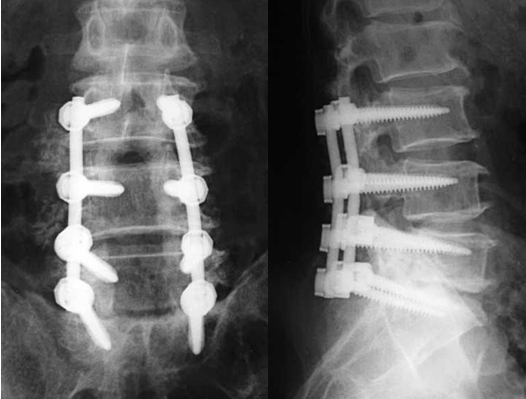

手术治疗手术的目的是解除神经组织和血管在椎管内、神经根管内或椎间孔内所受的压迫。出现下述情况时考虑手术治疗:

腰椎管狭窄症手术是国药东风总医院脊柱外科常规手术。脊柱外科一直秉承脊柱结核的规范化手术:采用传统常规治疗方式包括椎板开窗、半椎板切除、全椎板切除等,也可以采用微创技术治疗。常用的手术方式为椎板切除、神经根减压术,对于需要“减压+固定”病例可以采用传统常规治疗方式,也可以采用微创技术治疗。而融合技术可以选用横突间后外侧融合技术、椎板间后侧融合技术、椎间融合技术等。脊柱外科对腰椎管狭窄症的治疗,积累了丰富的临床经验,手术难度也逐年上升、复发率大幅度下降。